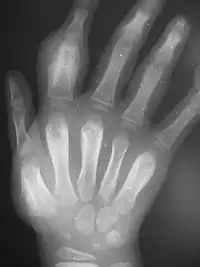

Secondary yaws affects the skin and bones.[12] The most common bone-related problem is periostitis, an inflammation around the bone, often occurs in the bones of the fingers and the long bones of the lower arm and leg, causing swollen fingers and limbs.[12] This causes pain at night and thickening of the affected bones (periostitis).[2] 75% of infected children surveyed in Papua New Guinea reported joint pain.[2] Swollen lymph nodes, fever, and malaise are also common.[12]